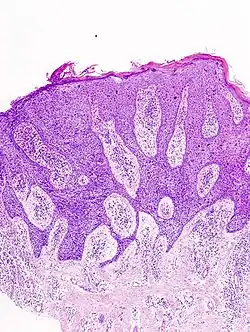

In situ disease

Bowen's disease is essentially equivalent to and used interchangeably with cSCC in situ, when not having invaded through the basement membrane.[12] Depending on source, it is classified as precancerous[13] or cSCC in situ (technically cancerous but non-invasive).[48][49] In cSCC in situ (Bowen's disease), atypical squamous cells proliferate through the whole thickness of the epidermis.[12] The entire tumor is confined to the epidermis and does not invade into the dermis.[12] The cells are often highly atypical under the microscope, and may look more unusual than the cells of some invasive squamous-cell carcinomas.[12]

cSCC in situ -

cSCC in situ